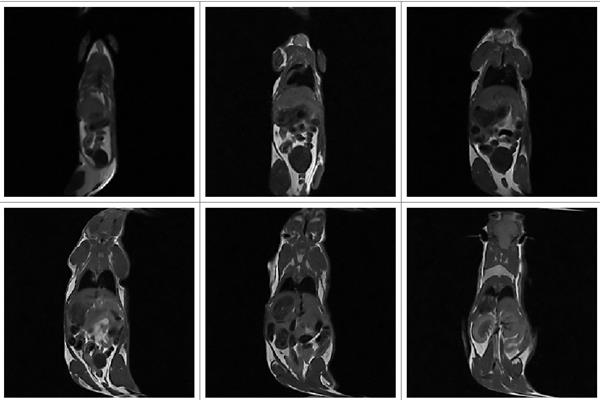

NM-G1小鼠冠狀面成像(層厚1.0mm)

1.0T小動物核磁共振成像儀NM-G1

更高分辨率,圖像更清晰

薄層任意層面任意角度掃描,最薄0.8mm

1.解剖結(jié)構(gòu)成像:腎臟體積大小

2.腫瘤:腫瘤大小,藥物對腫瘤的治療效果評價

3.造影劑成像:造影劑體外成像,活體內(nèi)的造影劑作用評價,造影劑體內(nèi)代謝監(jiān)測

4.脂肪分布:肥胖癥、營養(yǎng)學(xué)等相關(guān)研究

5.藥理:納米載藥在體內(nèi)的作用及代謝評價,特異性藥物載體靶向性判定